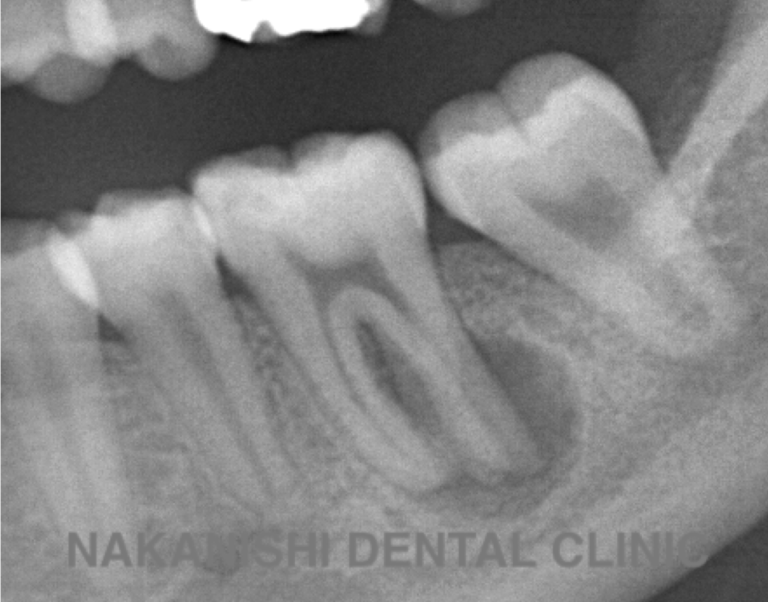

治療前

治療後

| 主訴 | 左下奥歯が痛い、歯ぐきの腫れ。 前医で抜歯を提案されたがセカンドオピニオン希望でご来院。 |

|---|---|

| 治療期間 | 約半年(6か月) |

| 治療費 | 約5万円 |

| 治療内容 | 前医ではラバーダム不使用であったため、ラバーダム、マイクロスコープ下にて根管治療を施術。 痛みは消失したが腫れは治らなかったため、意図的再植を行い腫れは消失した。治療後のレントゲンは意図的再植後3年経過したもの。 |

| 治療のリスク | マイクロスコープやCTを使用し、可能な限り精密な根管治療を行っていますが、歯根の形態や病変の大きさ、過去の治療履歴などにより、治癒が得られない場合があります。 また、治療後に再感染や歯根破折が生じることもあり、その場合は再治療や抜歯が必要となることがあります。 治療結果には個人差があり、すべての症例で同様の経過を保証するものではありません。 |